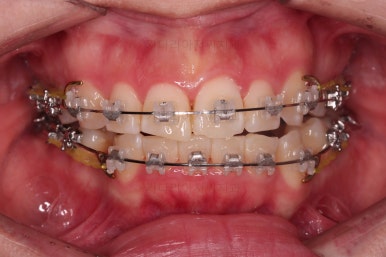

동래교정치과 마무리 사진입니다.

종료 이후에는 어금니의 기존 크라운 보철이 오래되고 탈이나서 재보철을 해주었습니다.

앞니는 비뚠채로 장기간 마모가 되어온 터라 형태가 부적절하긴 한데요.

보철로 마무리하기 보다는 최대한 자연스럽게 시리지 않는 선에서 다듬어 드리고 마무리를 했습니다.